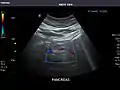

Abdominal ultrasound can be used to diagnose abnormalities in various internal organs, such as the kidneys,[1] liver, gallbladder, pancreas, spleen and abdominal aorta. If Doppler ultrasonography is added, the blood flow inside blood vessels can be evaluated as well (for example, to look for renal artery stenosis). It is commonly used to examine the uterus and fetus during pregnancy; this is called obstetric ultrasonography.[2][3]

Renal ultrasonography

Ultrasonography of the kidneys is essential in the diagnosis and management of kidney-related diseases. The kidneys are easily examined, and most pathological changes in the kidneys are distinguishable with ultrasound.[7]